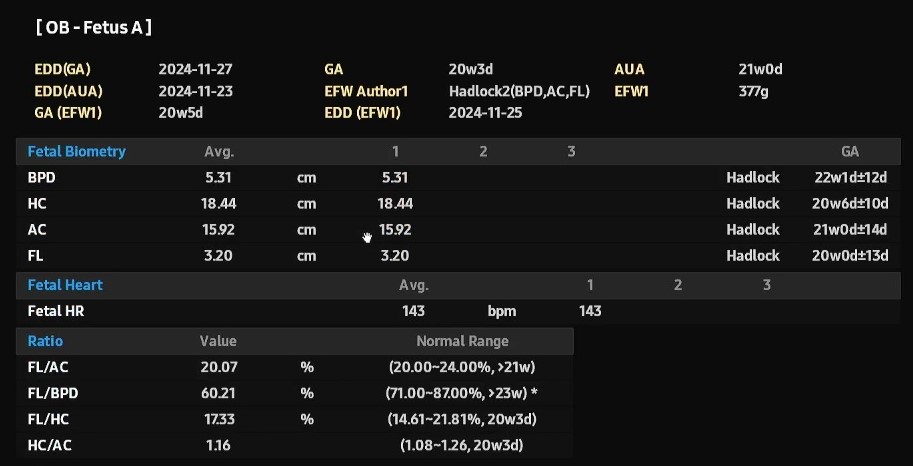

쑥쑥이는 377g, 쭉쭉이는 327g으로 둘의 차이는 13.09%로 저번보다 차이는 많이 나지만 20%넘으면 안좋다고 하셨어요.